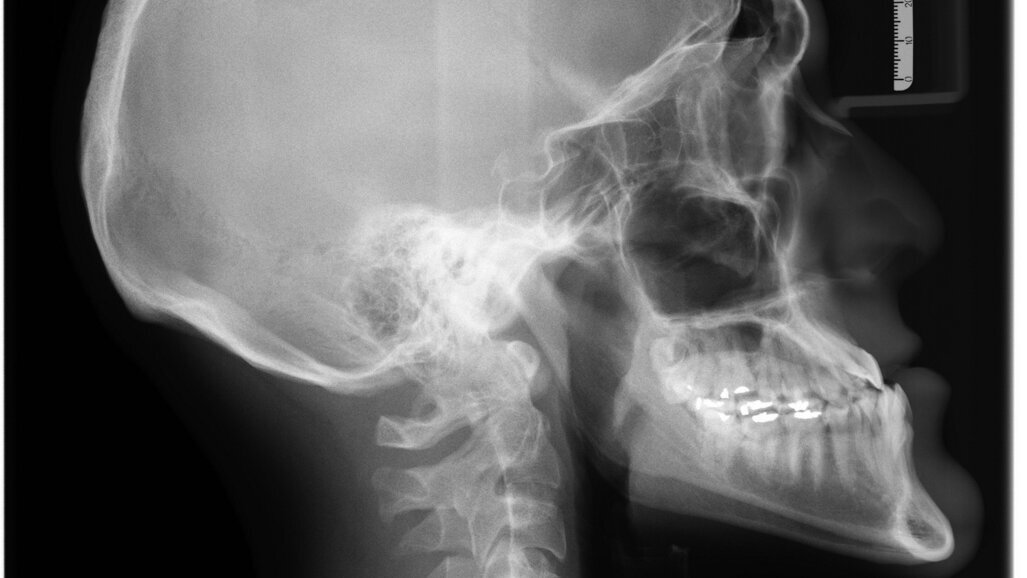

- zdjęcia cefalometryczne,